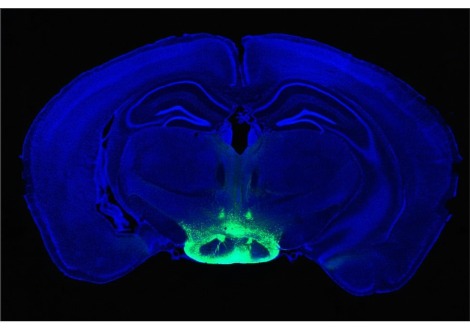

يُفسد زولبيديم، المعروف باسم أمبين، وظيفة أخرى محتملة من وظائف النوم، ألا وهي تنظيم النوم. كل 20 ثانية تقريبًا، تنبض موجة من السائل النخاعي عبر دماغ الشخص النائم. يشتبه العلماء في أن هذه النبضات الإيقاعية تُزيل الفضلات، بما في ذلك البروتينات اللزجة التي تتراكم في مرض الزهايمر.

يشبه هذا الغسيل الدماغي تشغيل غسالة الأطباق طوال الليل، كما تقول عالمة الأعصاب مايكن نيدرجارد، التي ساهمت في اكتشاف هذا النظام. غسل الأطباق ليس مهمةً براقة، بل مهمةً مهمةً لم تُقدّر تمامًا. وتضيف: "لقد تم تجاهل وظيفة النوم التنظيمية بأكملها لسنواتٍ طويلة".

تقول نيدرجارد، من جامعة روتشستر في نيويورك وجامعة كوبنهاغن، إن الفئران التي تناولت زولبيديم نامت أسرع وأعمق من الفئران التي تنام بشكل طبيعي. لكن غسلها كان أقل قوة، وفقًا لتقرير فريقها في مجلة Cell في 6 فبراير.